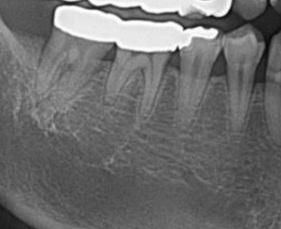

확인부탁드립니다. 아무리봐도 과잉같아요

아무리찾야봐도 뼈가녹은것같지도 염증이잇는것같지도않은데

치아뿌리에 금이갓다는얘기는못들엇고. 사랑니뽑은이후로 영향을받은것같다 옆치아에 영향주기전에 발치하자합니다 과잉진료인가요,,,?

흔들리는진단은 10년전에도 받은적이잇어요 오른쪽 맨끝 신경치료안한 어금니에요

• 1번 째 사진

뼈는 녹아 있는 것이 확인됩니다. 치아를 살리시고 싶으시면 잇몸치료 선행해보셔도 괜찮습니다.